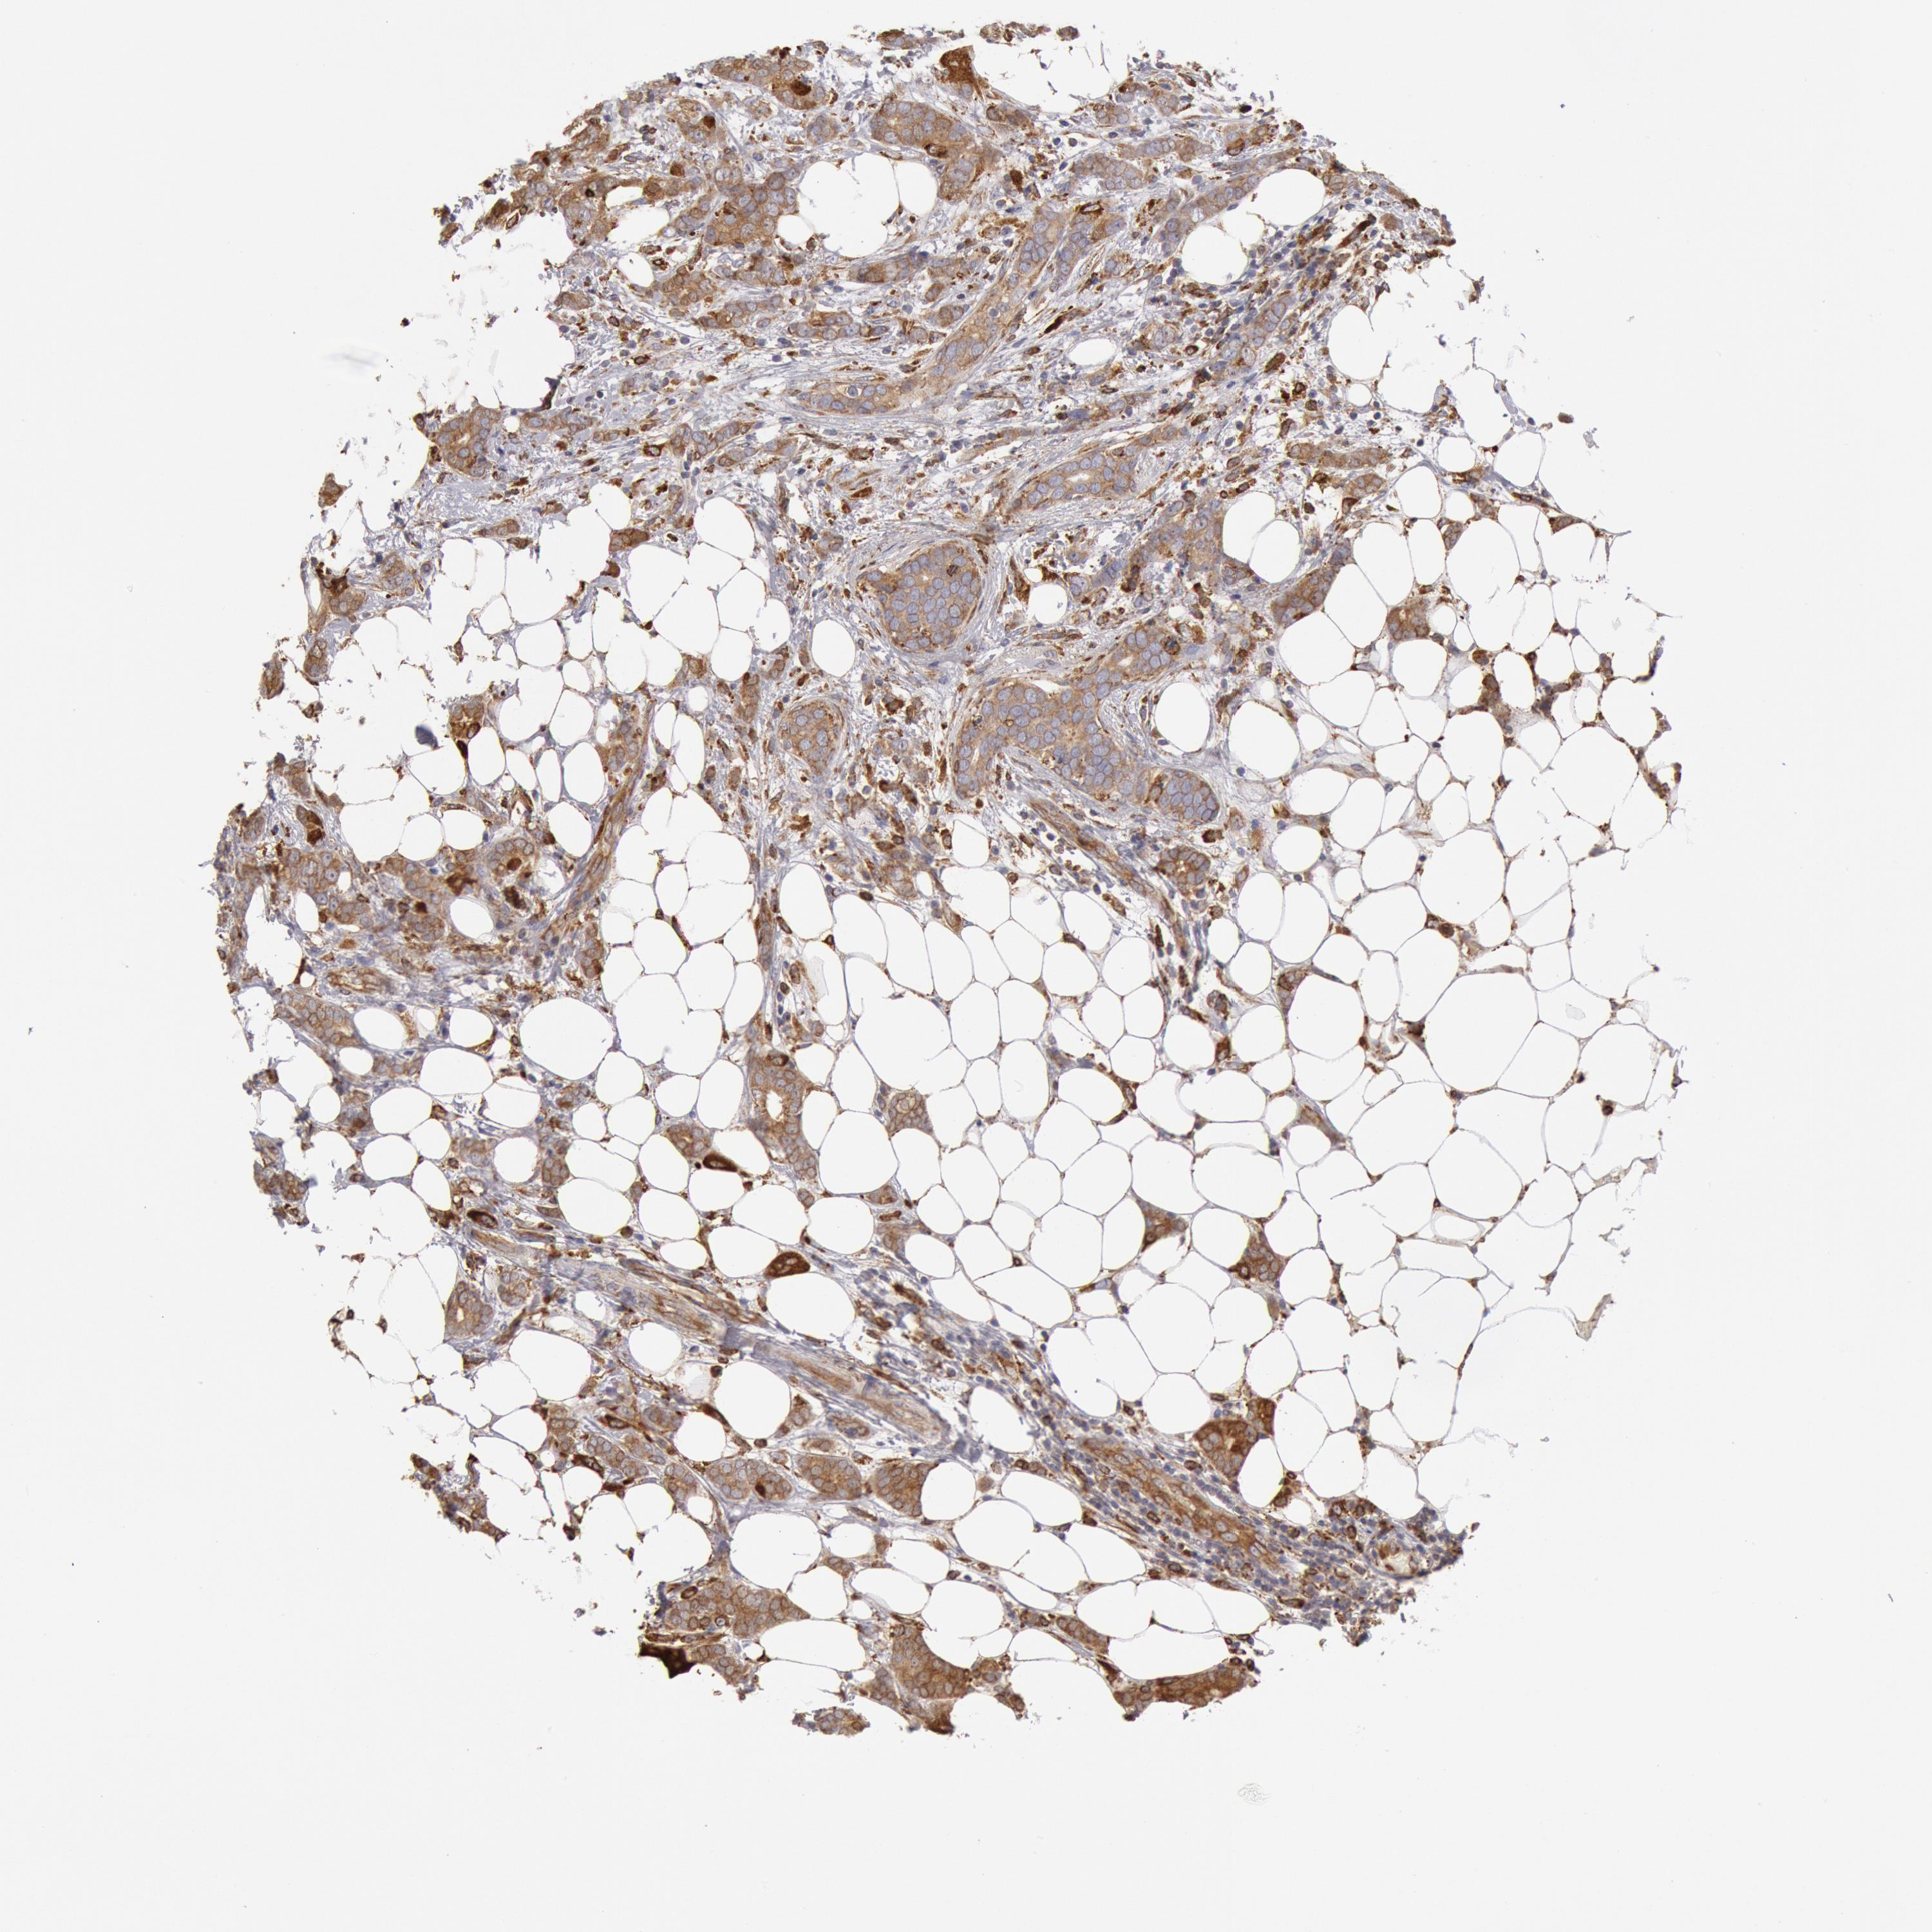

BRCA TCGA BRCA VALIDATION PROTEIN EXPRESSION